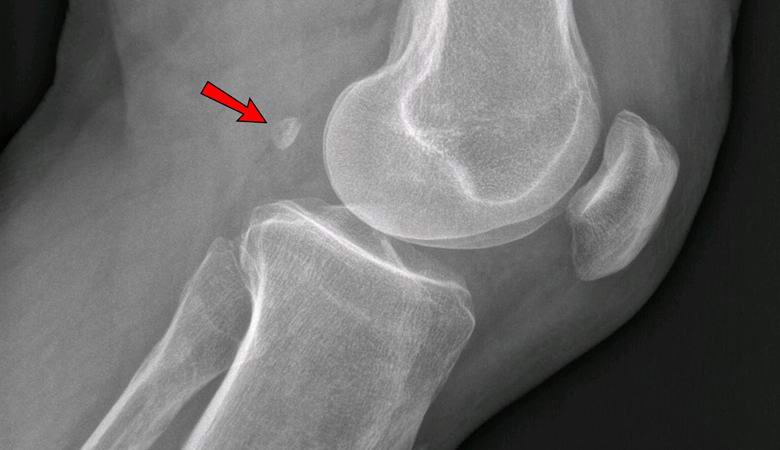

Če je leta 1918 le 11% Zemljanov imelo fabelo v vsaj enem noga, danes je prisotna pri 39% ljudi. Ta je v obliki sezama kost raste v debelini tetiv za kolenom in anatomsko spominja na mikroskopsko patelo.

Zdravniki še vedno ne morejo določiti, zakaj je to rudiment se vrača v človeško telo in zakaj je to potrebno. Najprej zdravniki so menili, da je Fabella le neškodljiv, nepotreben organ, vendar so strokovnjaki zdaj ugotovili, da je njena prisotnost v kolenu lahko povzroči osteoartritis. Bilo je celo zdravnikov ki je priporočal vsem, ki imajo fabelo, da jo odstranijo kirurško, da ne bi v starosti trpeli zaradi deformacije osteoartritis.

Danes vsak učbenik biologije kaže, da je človeški okostnjak sestavlja 206 kosti. Vendar pa bodo v prihodnosti morda takšni podatki prepoznani kot zastareli, in tam bodo govorili o 206-208 kosti, saj veliko ljudi že ima eno ali obe basni. Tole kost, mnogi zdravniki menijo, lahko imenujemo priloga okostje, “ker ni samo neuporaben, ampak lahko tudi služi povzročajo zdravstvene težave. V stiku s kolenskim hrustancem oz. vodi v hud osteoartritis.